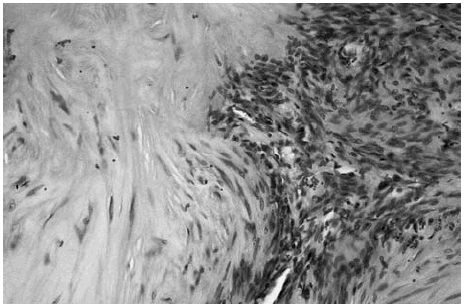

Las áreas hipocelulares presentaban un estroma escleroso. Las células que contenían se disponían en haces no muy bien estructurados. Estas células mostraban un núcleo alargado con extremos redondeados que recordaban fibras musculares lisas (fig. 4).

Fig. 4.--Detalle de una transición entre una zona hipocelular con células fusiformes dispuestas en haces no muy bien estructurados con un estroma hialinizado y una zona hipercelular.